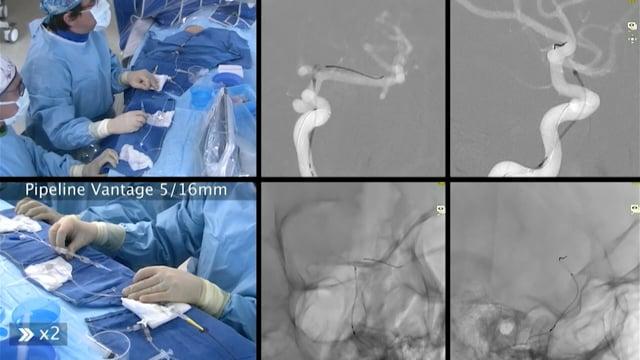

One&Done technique with optiMAX large volume coil

Stent assisted coilingAneurysms